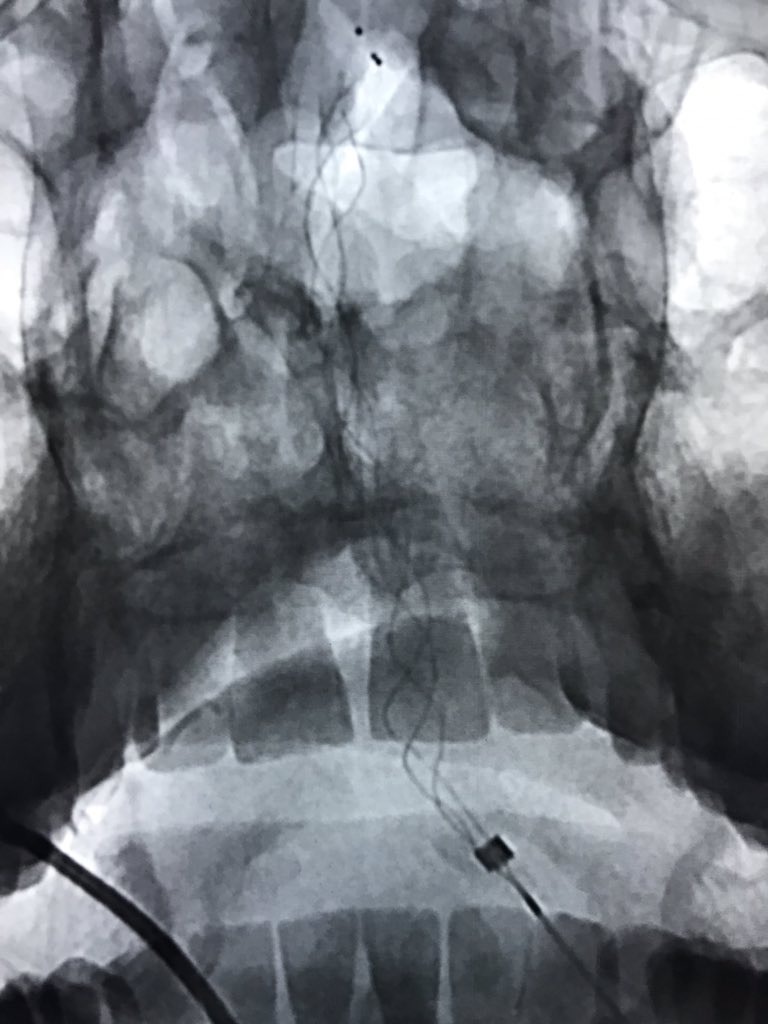

Tortuous Left CCA Origin. sim 2 to rescue.

#acutestroke#LVO pic.twitter.com/MR6HUiM4R5Show this thread -

Basilar occlusion with waxing and waning symptoms and underlying intracranial atherosclerosis. One pass with the 4x30 Trevo and ACE60 with the neuron max in the vertebral. Small new territory embo to the left superior cerebellar

#IRad#MIIPS#LVO pic.twitter.com/tpuYaHJfoC